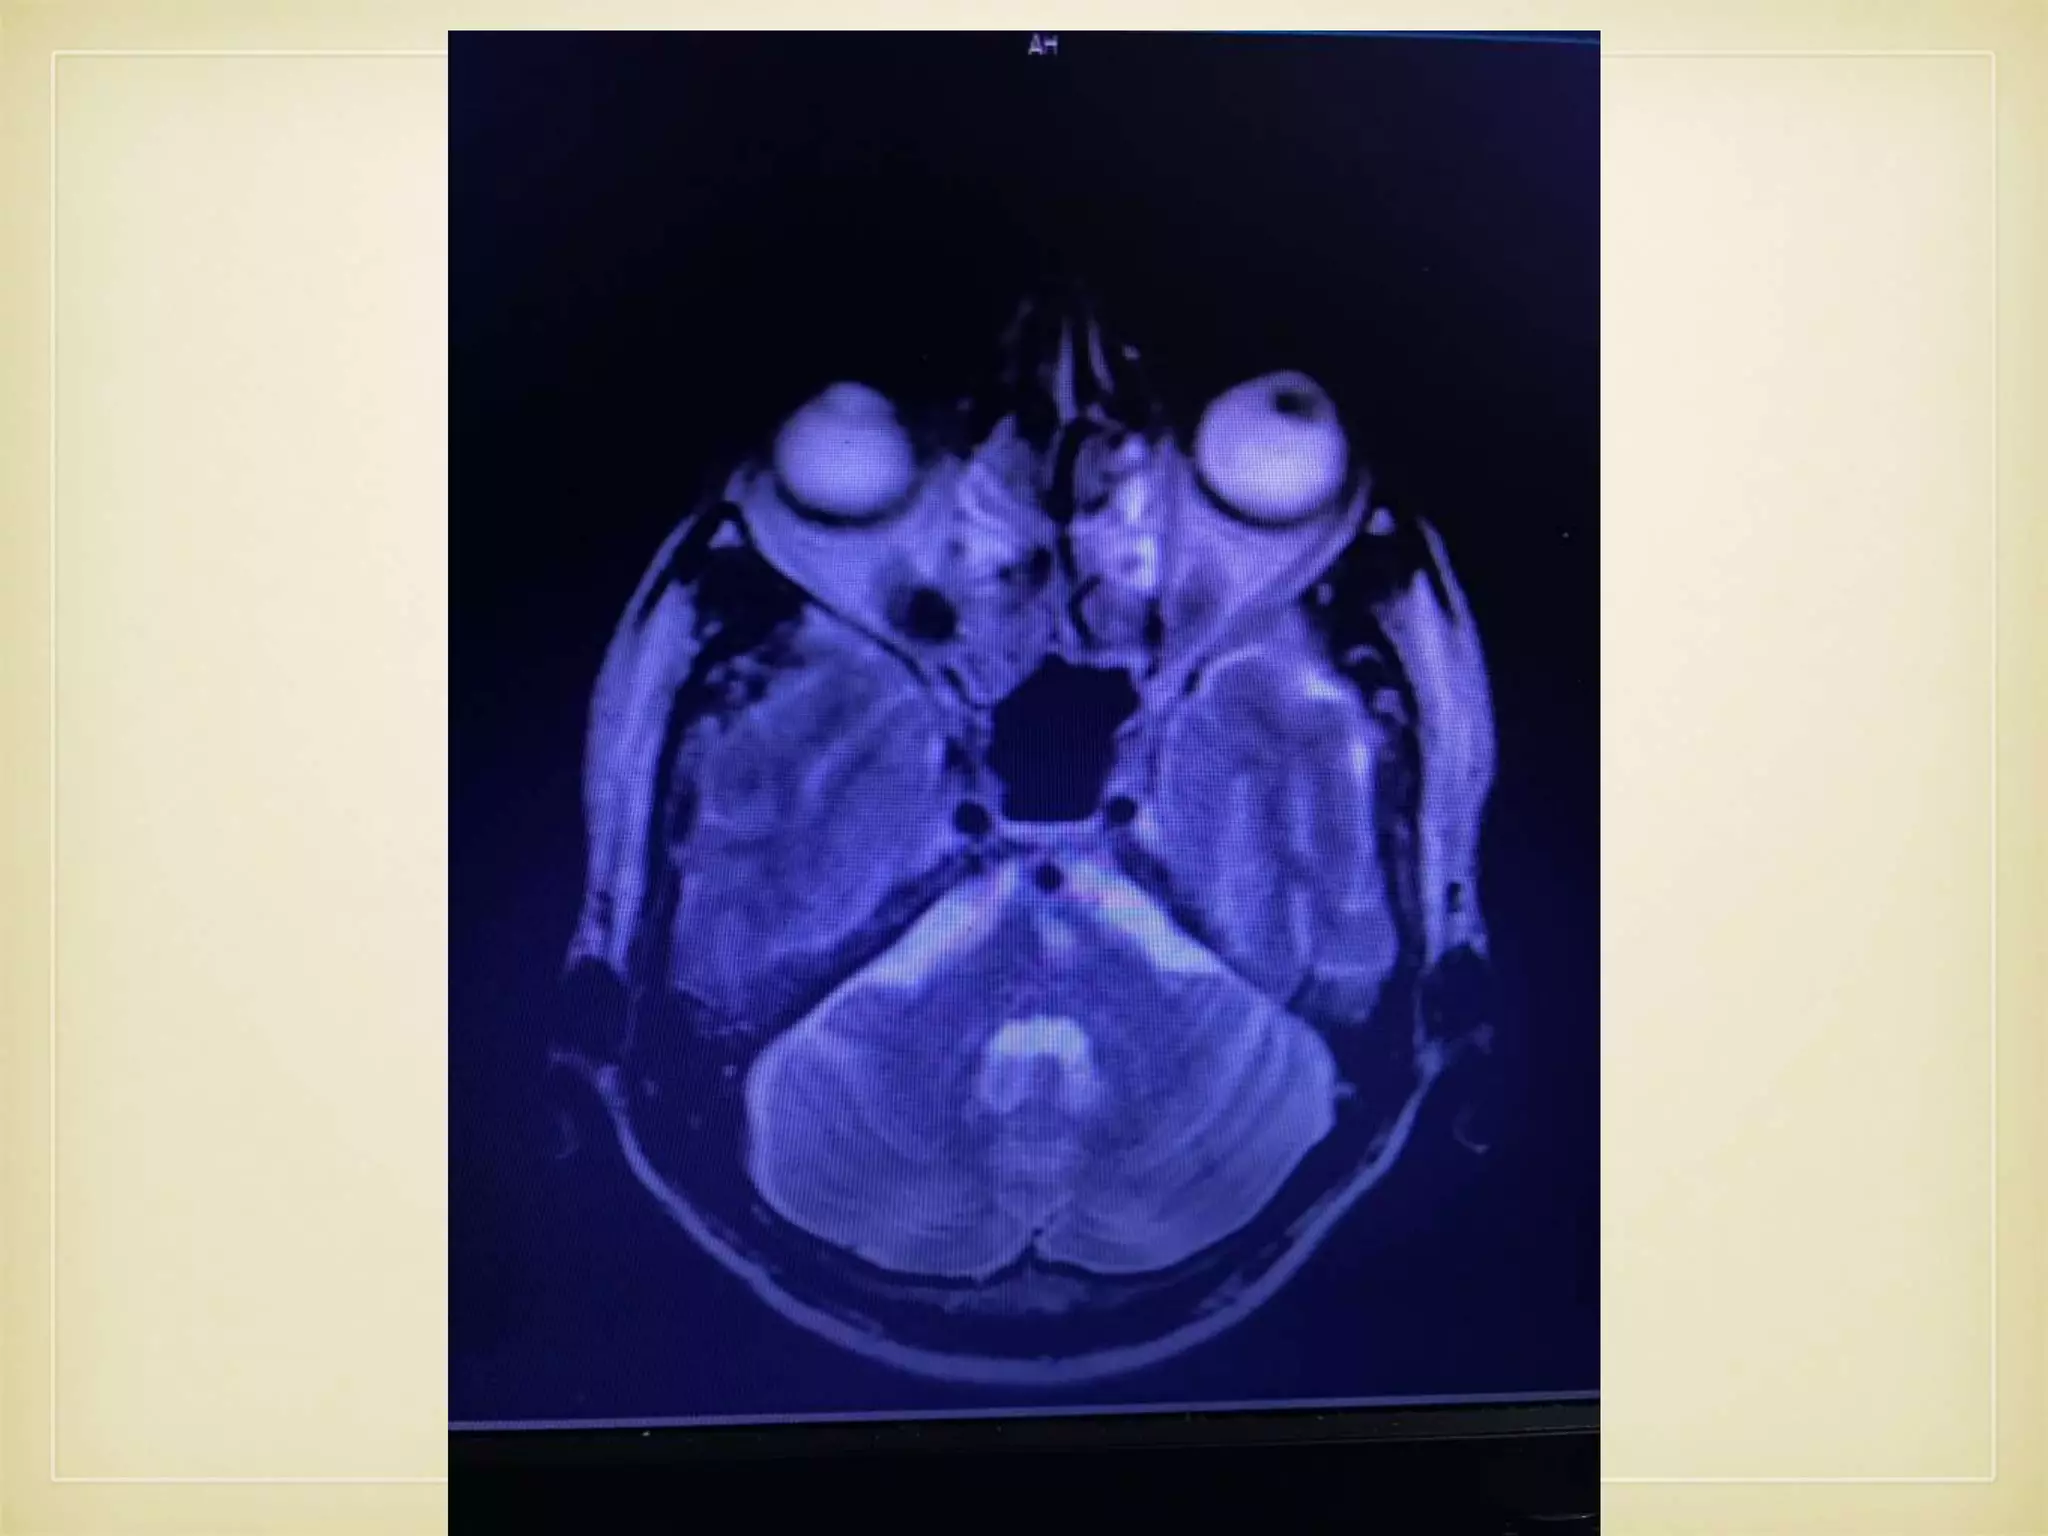

• Further evaluated with MRI brain and MRA

IMAGING

• CT Brain- SDH Rt. Fronto-temporo-parietal region • MRI C.Spine - C4-5, C5-6 disc bulging with compression of C5/6 roots on R>L with facet joint hypertrophy

• Again Readmittedon 22.12.2107 with ℅ Paroxysmal Dysarthria - 2 times lasting for 10- 15 times and recovers fully. • No other associated symptoms • Further evaluated with MRI brain and MRA